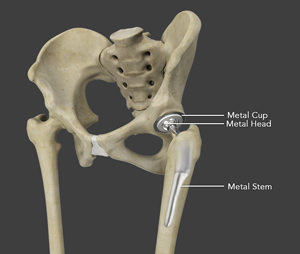

The surgery is performed under general anesthesia. During the procedure, a surgical cut is made over the hip to expose the hip joint and the femur is dislocated from the acetabulum. The surface of the socket is cleaned and the damaged or arthritic bone is removed using a reamer. The acetabular component is inserted into the socket using screws or occasionally bone cement. A liner made of plastic, ceramic or metal is placed inside the acetabular component. The femur or thigh bone is then prepared by removing the arthritic bone using special instruments, to exactly fit the new metal femoral component. The femoral component is then inserted to the femur either by a press fit or using bone cement. Then the femoral head component made of metal or ceramic is placed on the femoral stem. All the new parts are secured in place using special cement. The muscles and tendons around the new joint are repaired and the incision is closed.